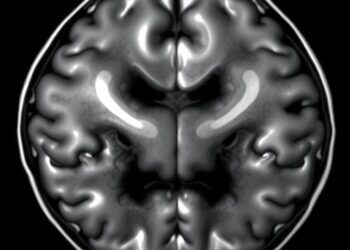

Exploring U-Net Variants for MRI Brain Tumor Segmentation

In the ever-evolving landscape of medical imaging, the need for precise and efficient segmentation of brain tumors from MRI scans ...